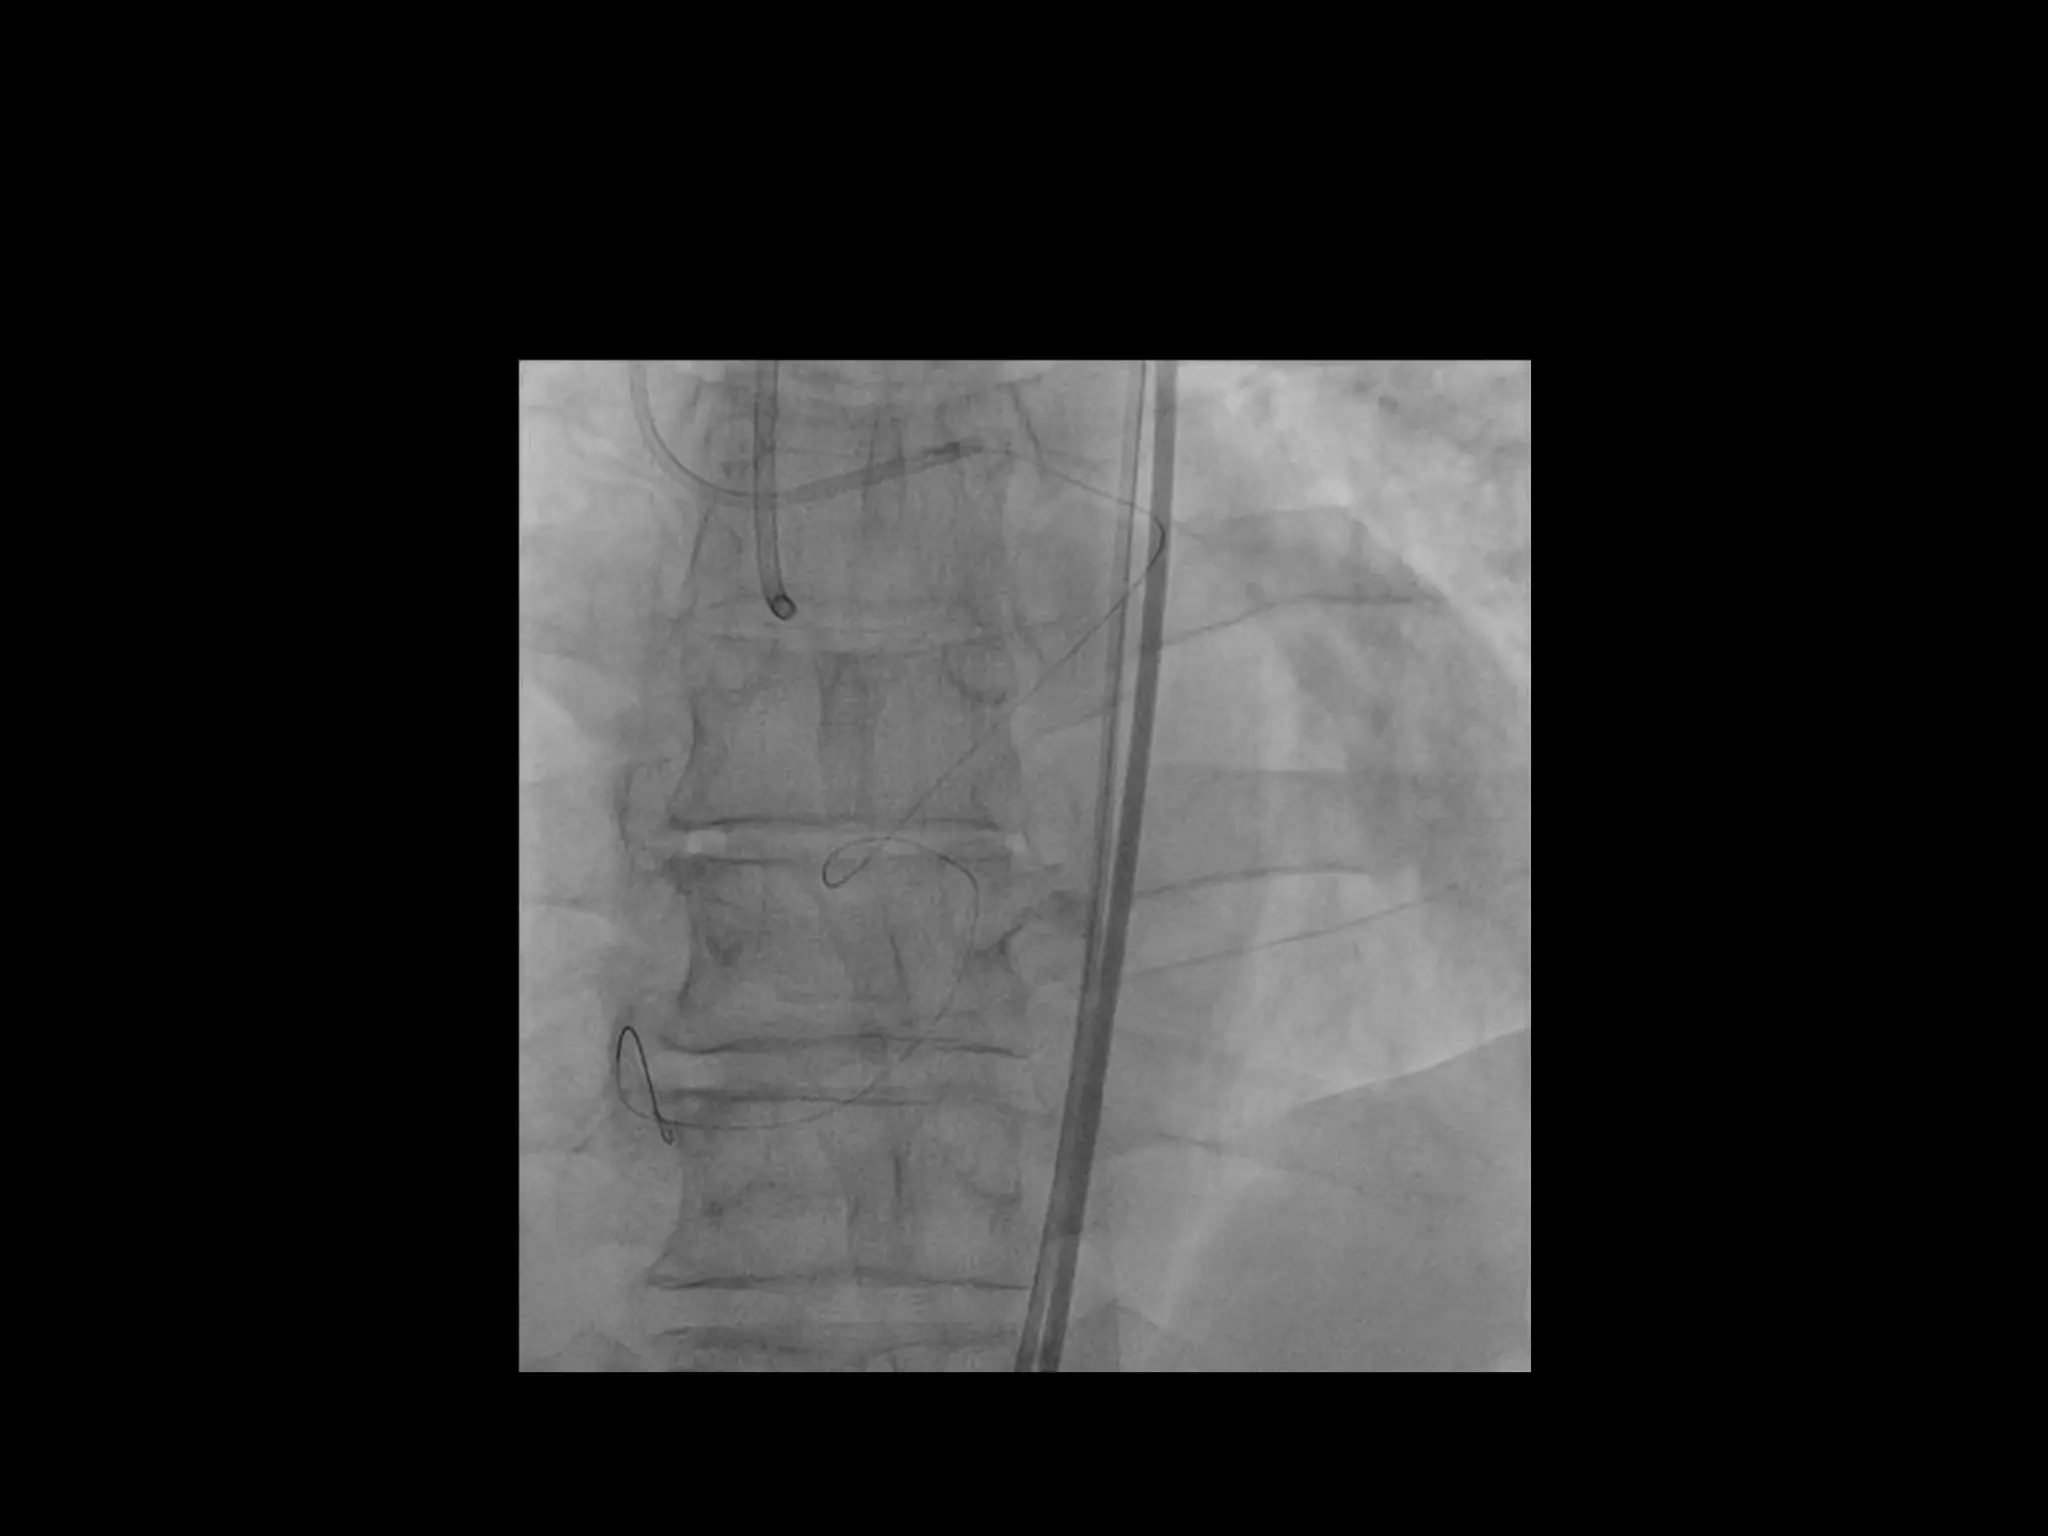

This document provides guidance on evaluating the feasibility of percutaneous coronary intervention (PCI) for a chronic total occlusion (CTO). Key factors to consider include: the patient's tolerance for a long procedure, contrast load, and radiation exposure; the CTO's proximal cap ambiguity, length, distal landing zone, and presence of interventional collaterals; and ensuring good quality angiography. With adequate planning and use of appropriate CTO techniques, feasibility is nearly always present for symptomatic patients. Success rates of CTO-PCI are reported to be 94% when using a planned approach.